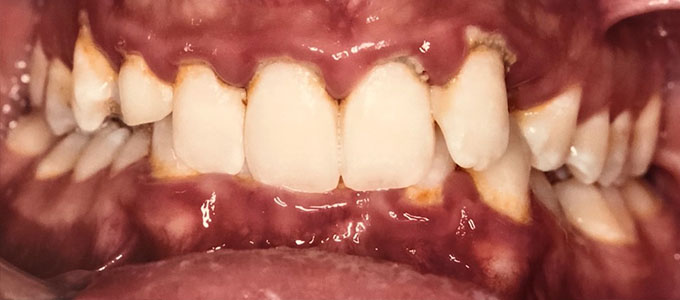

Un zâmbet frumos

Un zâmbet frumos este roada tratamentului ortodontic de succes dar pentru a se ajunge la acest rezultat sunt necesare mai multe etape care trebuie parcurse pas cu pas.

Tratamentul ortodontic este un proces biologic complex care include modificări ale oaselor maxilare, faciale și ale țesuturilor moi pe măsură ce dinții sunt mișcați în noile poziții.

Tratamentul ortodontic nu este o soluție rapidă. Acesta începe întotdeauna cu o examinare minuțioasă a dinților, a buzelor și a întregului aspect facial, sunt necesare radiografii si fotografii de diagnostic. Din aceste informații detaliate medicul ortodont dezvoltă un plan de tratament personalizat.